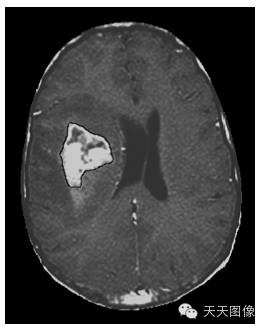

下面只上几张比较中规中矩的肿瘤图像。

上面是一些典型的脑肿瘤图,图中的白块就是肿瘤。为了让大家看的更直观,特地选出来一些比较好分割的图像,但是也并不是什么方法都能分割出来的,就我个人知识而言,不进行任何预处理,没有一种方法可以自动地直接将这些肿瘤都给分割出来。不信可以去问问周边搞图像的人,如果有,请务必告诉我。

下面是我的分割结果,算不上完全自动,但是也是基本上不需要监督。(仔细看肿瘤周围叠加的轮廓,就是分割的结果)

用到的方法就是水平集。